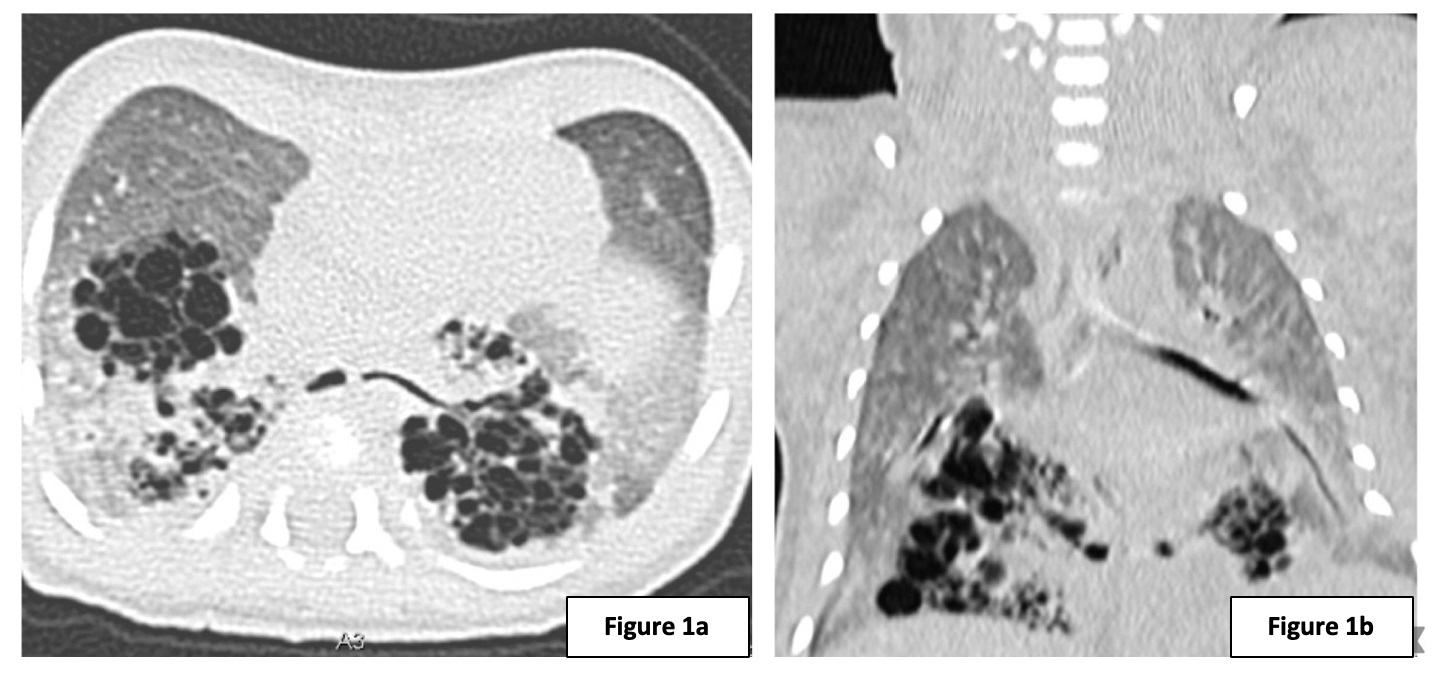

The patient had poor weight gain and at 7 months of age underwent a left posterolateral thoracotomy with lower left lobectomy and chest tube placement. Postoperatively, he had non-invasive mechanical ventilation in the surgical ICU that was gradually weaned. The chest tube was removed on the 6th postoperative day. Histopathology revealed another type 2 congenital pulmonary airway malformation (Fig. 2a). Postoperative chest X-ray showed adequate lung expansion without evidence of pneumothorax (Fig. 2b). The patient was discharged asymptomatic on the 15th postoperative day and is currently being followed up through regular outpatient visits. The follow-up visits included consultations at 15 days and 2 months post-surgery. A long-term follow-up is planned.

a) Lung lobe with dilatation of cysts lined by respiratory epithelium, without mucus cells and cartilage, and atelectasis of adjacent parenchyma. Consistent with CPAM type 2. b) Postoperative chest radiograph.